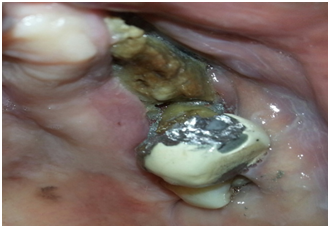

Over 60 year-old Sudanese woman knowledgeable with jaw problems initiate 12 months ago with spontaneous deep pain in the maxilla at the buccal left side. Her dentist referred her to the department of Oral Surgery, Khartoum Teaching Dental Hospital, when he identifies an extended exposed bone with pus discharge. The patient mentioned that over the 7 preceding months, she developed severe pain combined with episodes of swelling in the palate, discharge from bridge in left side of the upper jaw that extend from the upper central incisors to the first permanent molar in addition to halitosis.10 The past medical history she is adiabatic; had breast cancer and experience a wide local excision and auxiliary clearance 3 years ago. A six cycle chemotherapy regime was given since 2012. And 7 months ago bone scan confirmed skeletal metastasis in the vertebral column (Figure 1) and 12 cycle chemotherapy regime was given on 2016 (Zometa 4mg/month) intravenously.11 The intraoral examination revealed; marked halitosis, swelling in the palate which tender and discharge (blood + pus) on pressing, mobile bridge, mobility grade 3 in 26 and a large bony defect (yellowish exposed bone) in the upper left quadrant of the maxilla mainly involving the buccal alveolus under bridge (Figure 2). No extra oral findings were detected. Orthopantomogram view showed detected an osteolytic region in the maxilla left side (Figure 3) and C.T scan detected left maxillary mucosal thickening with nasal mucosal thickening (Figure 4). Incisional biopsy under local anesthesia was carried out with a segment of palatal mucosa adjacent to the necrotic bone.12 The pathology report showed only (mucositis) inflammation with no evidence of ulceration or neoplasia. Ciprofloxacin 500mg was prescribed for one month together with Chlorhexidine mouth wash. An isolation of the sequestrum, with mobility of the 26 tooth was obtained. It was decided to remove the left maxillary first molar and sequestrum conservatively.

Figure 2 Shows pretreatment intraoral view (Yellowish exposed bone in the upper left side of maxilla).